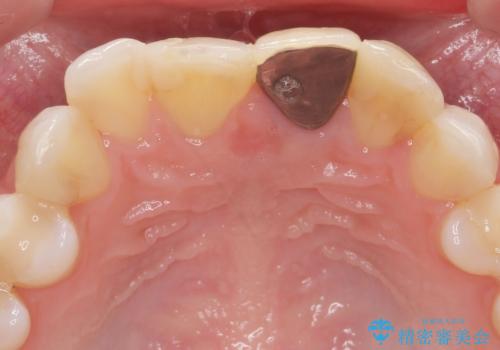

- 長年気になっている前歯の見た目を改善したいと来院されました。

両側の前歯に根尖性歯周炎を認めたため根管治療を行ったのち、ジルコニアクラウンを用いた審美性の改善を計画します。